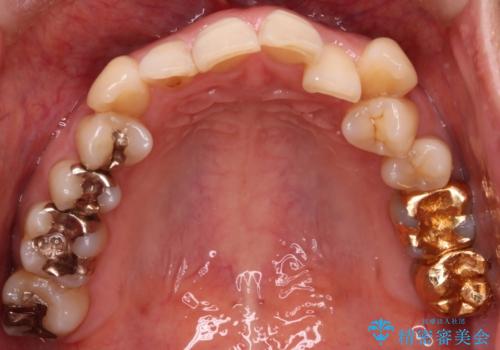

- 上下の歯の凸凹を主訴に来院されました。

他院では抜歯+ワイヤー矯正の提案をされているとのことでした。

当院での検査にて非抜歯+インビザライン矯正を提案させていただき治療を行なっております。